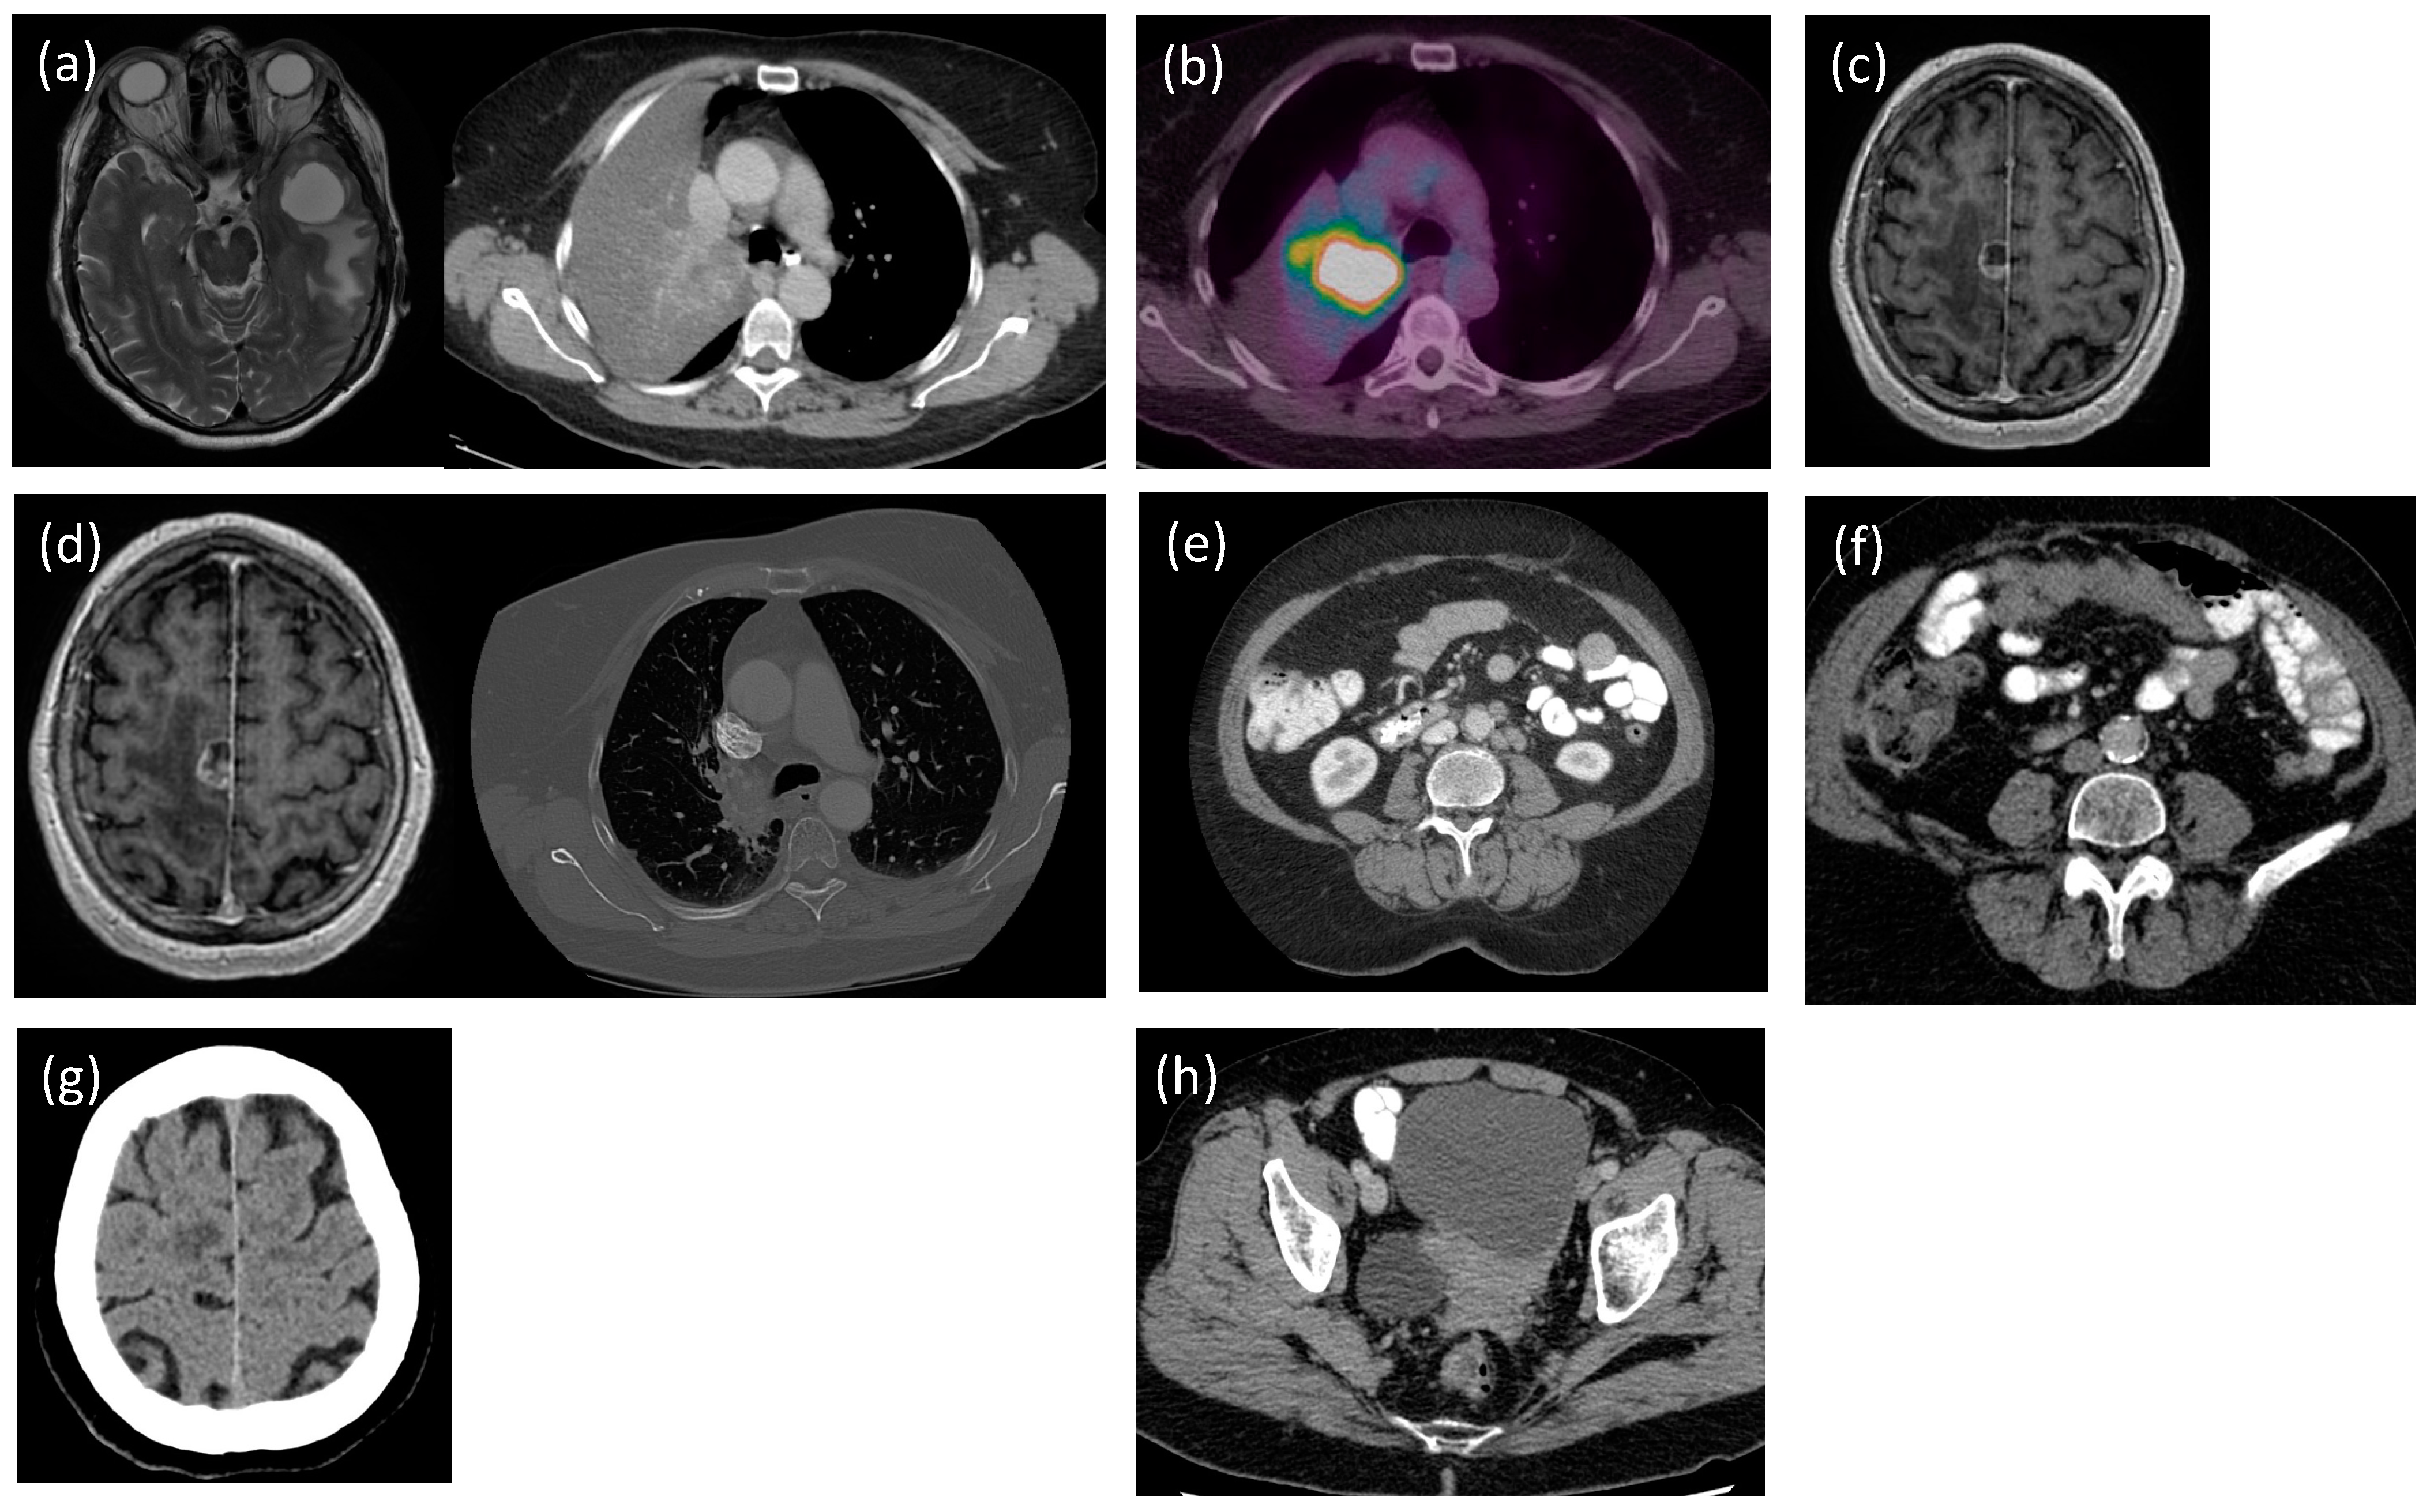

2.1. Non-Small Cell Lung Cancer (NSCLC)

2.1.1. Initial Presentation and Diagnosis

2.1.2. Therapeutic Interventions

2.2. Ovarian Serous Carcinoma

2.2.1. Initial Presentation and Diagnosis

2.2.2. Therapeutic Interventions

2.3. Follow-Up and Outcomes